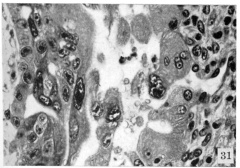

Detail of arteriovenous sinusoid

Arteriovenous sinusoid and capillary branch